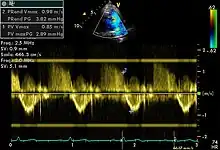

Spectral doppler

Spectral doppler is presented similarly to M-mode in which the doppler information is plotted as a spectrogram. This can be both "continuous" and "pulse" wave where the former shows the spectrum along a specific line and the latter shows within a small window along that line. Continuous wave is better at showing maximal velocities and pulse wave is better for showing flow through a small volume.

Spectral doppler is often used for quantification of flow. For example, the aortic valve area can be estimated using the continuity equation by measuring the velocity time integral (VTI) of the aortic valve & LV outflow tract; the VTI is calculated by tracing the flow on the spectral doppler curve. Spectral doppler is also useful for calculating the maximum flow and mean flow through a valve (used to grade valve stenosis).